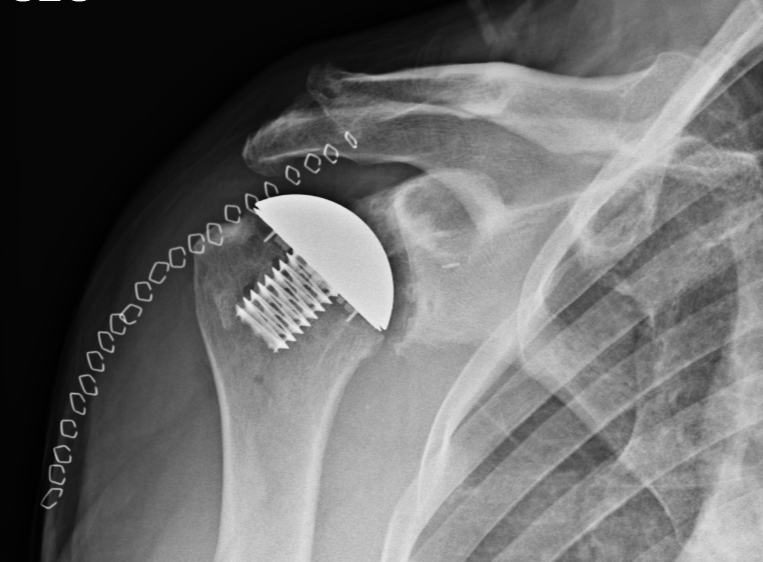

During David's follow up 10 days later, the X-rays demonstrated that everything looked well-aligned, and he reported to the staff that his pain was, "At most a 2/10." To assist with his recovery, David was scheduled for physical therapy, however because of his fast recovery, he quickly moved to once a week and was able to do most of his therapy at home.